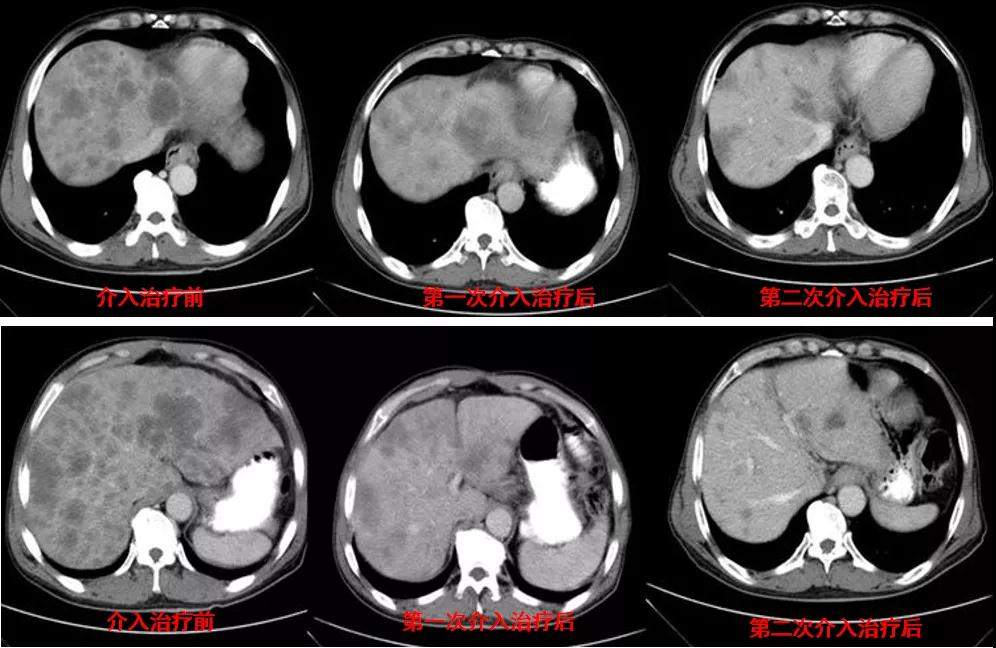

诊治经过:2020年12月16日患者行第二次经皮动脉化疗灌注栓塞术(铂类+氟尿嘧啶)治疗,并继续联合吡咯替尼治疗。结果见图3。

图3